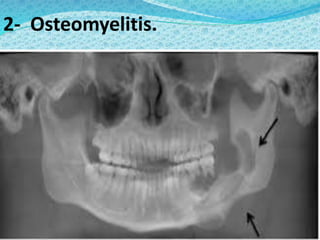

2- Osteomyelitis.

Diseases of thejaw 1- Fractures.

3- Infected bonecysts. 4- Malignant neoplasms. 5- Sickle cell infarcts.